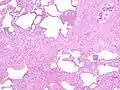

The histologic hallmarks of UIP, as seen in lung tissue under a microscope by a pathologist, are interstitial fibrosis in a "patchwork pattern", honeycomb change and fibroblast foci (see images below).[6] [7]

Appearance of usual interstitial pneumonia (UIP) in a surgical lung biopsy at low magnification. The tissue is stained with hematoxylin (purple dye) and eosin (pink dye) to make it visible. The pink areas in this picture represent lung fibrosis (collagen stains pink). Note the "patchwork" (quilt-like) pattern of the fibrosis.

Appearance of honeycomb change in a surgical lung biopsy at low magnification. The dilated spaces seen here are filled with mucin. Hematoxylin-eosin stain, low magnification.